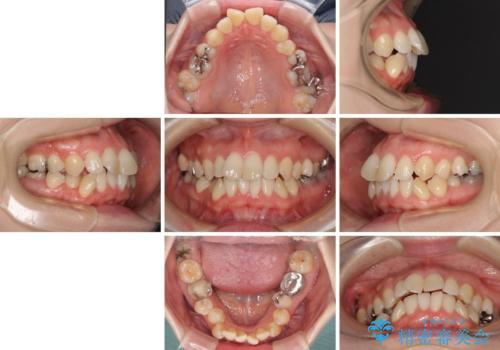

- 奥歯のむし歯を気にして来院された患者様です。

当初は右下の虫歯治療のみを希望されていましたが、虫歯治療に際して部分矯正が必要であったため、治療方法について説明をすると、全体的に歯列不正が気になっているとのことで、全顎矯正を検討することとなりました。

口元の突出感とデコボコがあり、上下左右の小臼歯4本を抜歯して矯正治療を行う方針としました。(右上は欠損のため計3本抜歯)

むし歯となっている歯は状態が悪く、将来的に抜歯となる可能性が高かったため、定石で抜歯させる小臼歯の代わりにむし歯となっている大臼歯を抜歯し、ワイヤー装置にて矯正治療を行うこととしました。